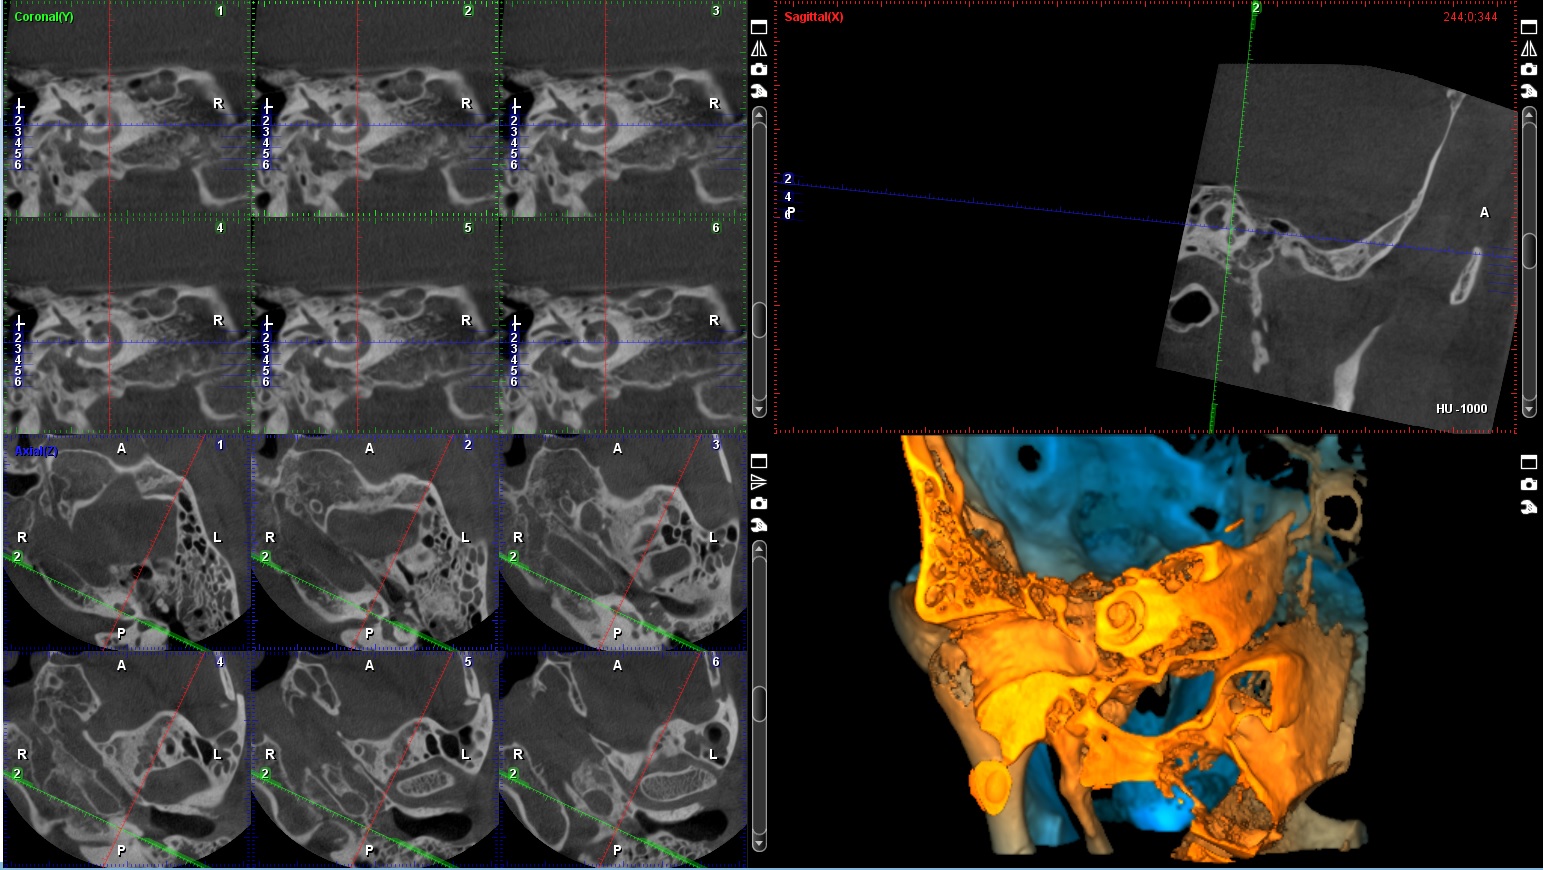

3D snimanje zuba, poznato kao konusni snimak (Cone Beam Computed Tomography – CBCT), pruža detaljan trodimenzionalni prikaz zuba, vilice i okolnih struktura. Ovaj napredni rendgenski postupak omogućava visoku preciznost u dijagnostici i planiranju tretmana, kao što su implantati, ortodontski aparati, lečenje korena i hirurške intervencije. Korišćenjem Planmeca aparata, CBCT omogućava detaljnu analizu čak i najmanjih struktura, što pomaže stomatolozima da donesu tačne i efikasne odluke za svaki specifičan slučaj.

Količina zračenja tokom 3D snimanja zavisi od veličine skenirane oblasti i veličine vokselâ (voxel size). Za aparat Planmeca ProMax 3D Mid, koji je poznat po visokoj preciznosti uz smanjeno zračenje, prosečna doza zračenja za 3D snimanje zuba je približno 10–20 mikrosiverta (µSv). Ovo je značajno niže u poređenju sa tradicionalnim CT snimanjima, koja mogu imati doze zračenja od 100–200 µSv.

3D snimci kao na sajtu.

3D - SNIMCI